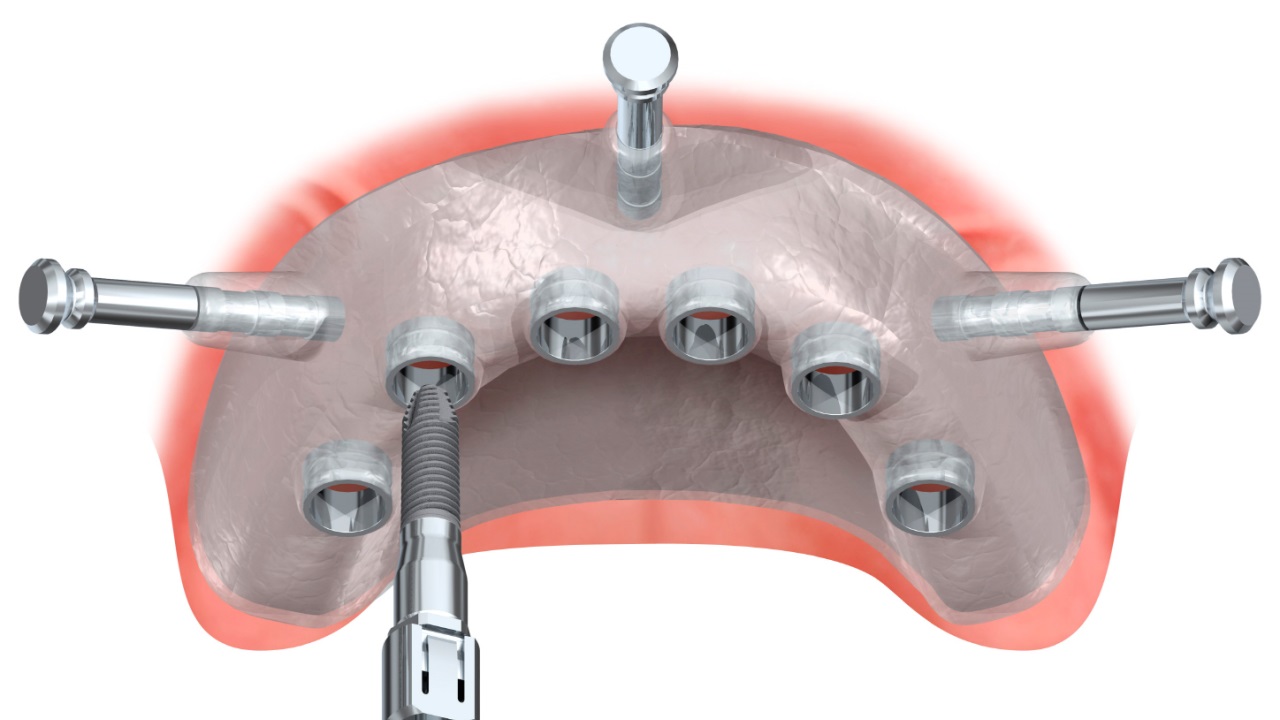

Пошаговое руководство по установке съёмного протеза на импланты